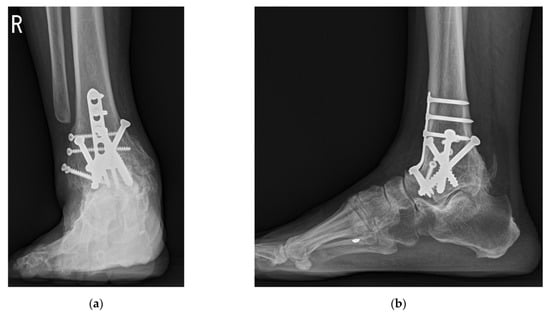

Union was obtained in all cases without additional surgery. The pre- and postoperative radiographic results are shown in Table 1. A total of 15 ankles (41.7%) had talar tilt of more than 15°, and 10 ankles (27.8%) had talar center migration of more than 8 mm in the coronal plane preoperatively (Figure 10). Eight ankles (22.2%) had an anteroposterior offset of more than 10 mm preoperatively. Talus center migration (p = 0.001), sagittal talar migration (p < 0.001), and hindfoot alignment angle (p = 0.001) significantly improved after surgery (Figure 11).

Figure 10. Preoperative weightbearing radiographs showed end-stage ankle arthritis with severe varus deformity: (a) anteroposterior view; (b) lateral view.